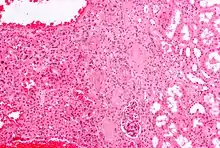

An oncocytoma is an epithelial tumor composed of oncocytes, large eosinophilic cells having small, round, benign-appearing nuclei with large nucleoli and excessive amounts of mitochondria.

The main differential diagnosis of renal oncocytoma is chromophobe renal cell carcinoma oncocytic variant, which like the renal oncocytoma has eosinophilic cytoplasm, but has perinuclear clearing and, typically, some degree of nuclear atypia.

Micrograph of a renal oncocytoma. H&E stain.